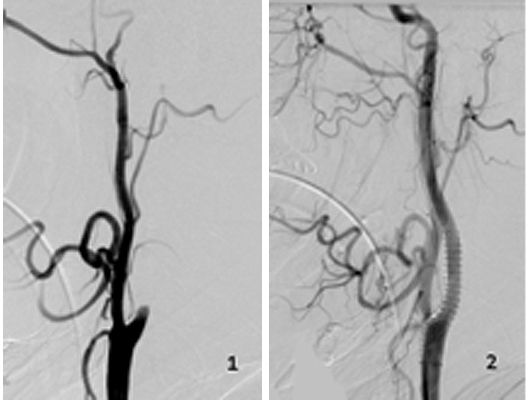

Mit den modernen Verfahren zur Wiedereröffnung von verschlossenen Blutgefäßen können wir Patienten mit Schlaganfall in vielen Fällen helfen. Das folgende Beispiel zeigt die angiographischen Bilder eines Patienten, der mit vollständiger Lähmung der rechten Körperhälfte und einer schweren Sprachstörung eingeliefert wurde. Ursächlich zeigte sich ein Verschluss der linken Halsschlagader, vermutlich auf dem Boden einer arteriosklerotischen Einengung (Bild 1). Das Gefäß wurde daraufhin mit einem Stent wiedereröffnet (Bild 2). Zusätzlich zeigte sich ein Verschluss der Endstrecke des Gefäßes durch Blutgerinnsel (Bild 3). Diese konnten vollständig entfernt werden (Bild 4). Der Patient erholte sich nach der Behandlung innerhalb weniger Tage vollständig.